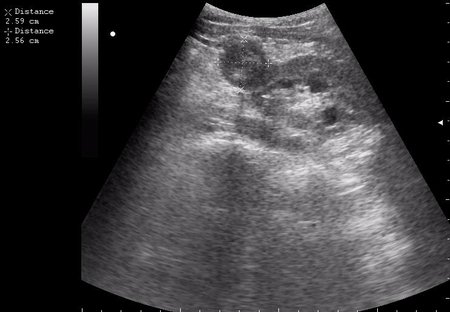

Гематома почки

нижний полюс